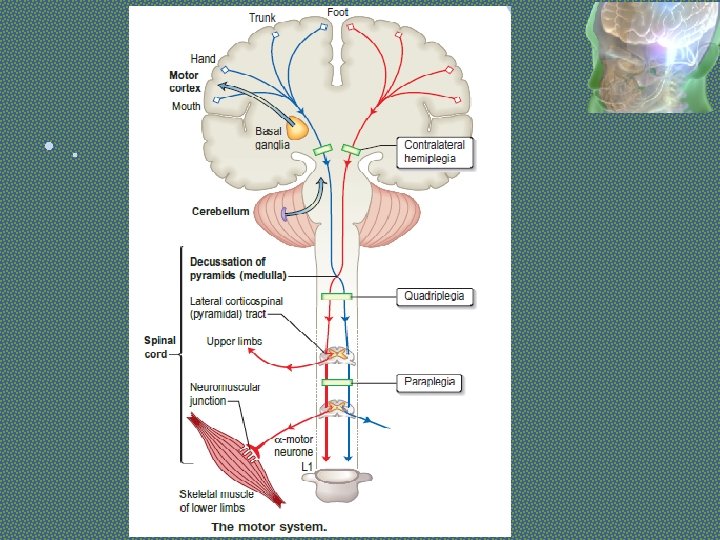

• UPPER MOTOR NEURONS (UMN) start from cerebral cortex, passes through internal capsule, corticospinal tracts, and ends at cranial nerve nuclei in brain stem or anterior horn cells of spinal cord at different levels. The axons of upper motor neurons are contained within the pyramidal system, which is composed of the corticospinal (pyramidal) and corticobulbar tracts. • LOWER MOTOR NEURONS (LMN) start from nuclei of cranial nerves or anterior horn cells of spinal cord, extend through cranial /spinal nerves and ends at motor end plate of concerned muscle.

Patterns of UMN disorders There are three main patterns: § HEMIPARESIS means weakness of the limbs on one side; it is usually caused by a lesion in the brain and occasionally in the cord. § PARAPARESIS means weakness of both lower limbs and usually diagnostic of a cord lesion; bilateral brain lesions occasionally cause paraparesis. § TETRAPARESIS (syn. quadriparesis) means weakness of four limbs.